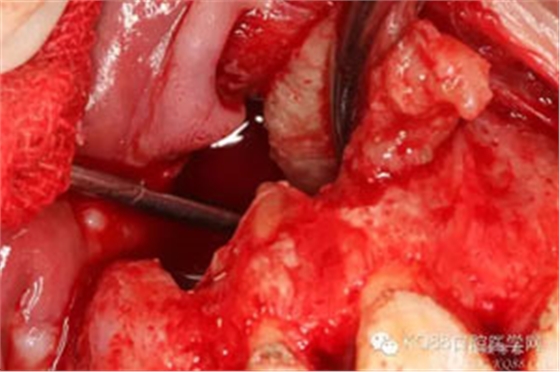

圖7.囊壁被完整摘除后遺留的巨大骨腔,11根尖牙膠尖依稀可見。

圖9.11/12/13的牙根完全裸露在囊腔內(nèi),13根尖牙膠尖超填過多。

圖10.超聲骨刀行11/12/13根尖切除術(shù)